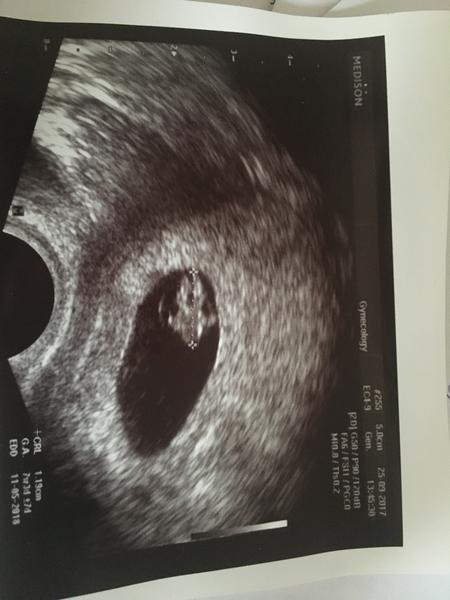

@volfici ahojky, míč ti gratuluji k miminku :* hcg jsem měla 2100. Bohužel mám hyperstimulak a 2 velké cysty 6cm na každém vaječníku. Navíc mám zvětšeny vaječník, tak hrozí přetočeni 😢😢😢 musím jen ležet. Já hyperstimulak ani nestudovala protože jsem měla minimální stimulaci. V tom šoku jsem se zapomněla zeptat dr. Z jakého důvodu hrozí přetočeni vaječníku, nevíš zda je to tím hyperstimul. Syndromem? Miminko mám vyfoceno na utz. Má 0,38cm.